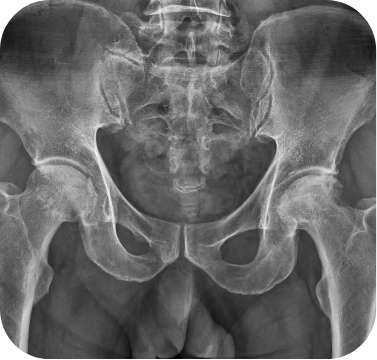

고관절 퇴행성관절염 환자의 인공관절 전치환술 사례

• ▲ 수술 전

• ▲ 수술 후